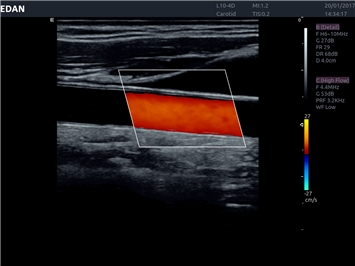

EDAN Acclarix LX4 представляет собой инновационную ультразвуковую систему, построенную на усовершенствованной платформе Acclarix. Сочетание высокого качества визуализации с интеллектуальным рабочим процессом делает эту систему оптимальным выбором для клиник, ценящих эффективность и экономичность.

• Сосудистой диагностики

Цветовой допплер:

Да